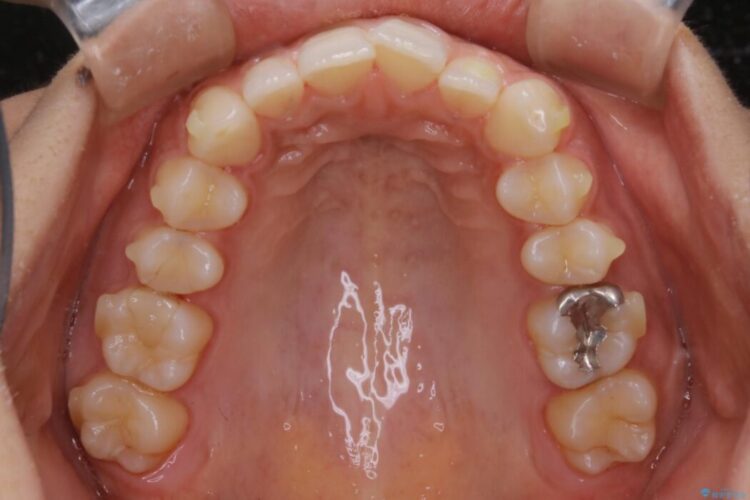

下の歯列よりも上の歯列が前に出ている状態を治すため、マウスピース矯正に加え、患者様にゴムかけのご協力をいただきました。その結果、ガタつきが改善し、上下の噛み合わせが適切な位置で合うようになりました。

歯列弓の拡大

歯並びが悪くなる原因の一つに「歯列弓の狭窄」というものがあります。

奥歯や前歯が内側(舌側)に倒れ込んでしまったり、歯が生えてくる位置が内側になってしまうことにより歯並びのアーチが狭くなってしまうことを言います。

このような場合、歯並びのアーチを拡大してあげるだけでもガタつきを無くすためのスペースがかなり作れることがあります。